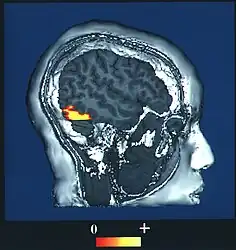

El área fusiforme de las caras, FFA (por sus siglas en inglés: Fusiform face area) es el principal sector del sistema visual del humano que está especializada para el reconocimiento facial.[1] Está localizada en la corteza cerebral temporal inferior (TI), en la circunvolución llamada giro fusiforme (área 37 de Brodmann).

El "área de rostro" FFA está localizada dentro de la red neuronal llamada corriente ventral ubicada en la superficie ventral del lóbulo temporal en la región lateral del giro fusiforme.

El área FFA es lateral y externa al "área de lugar" situada en el parahipocampo. La FFA muestra una cierta lateralización, usualmente siendo más grande en el hemisferio derecho.